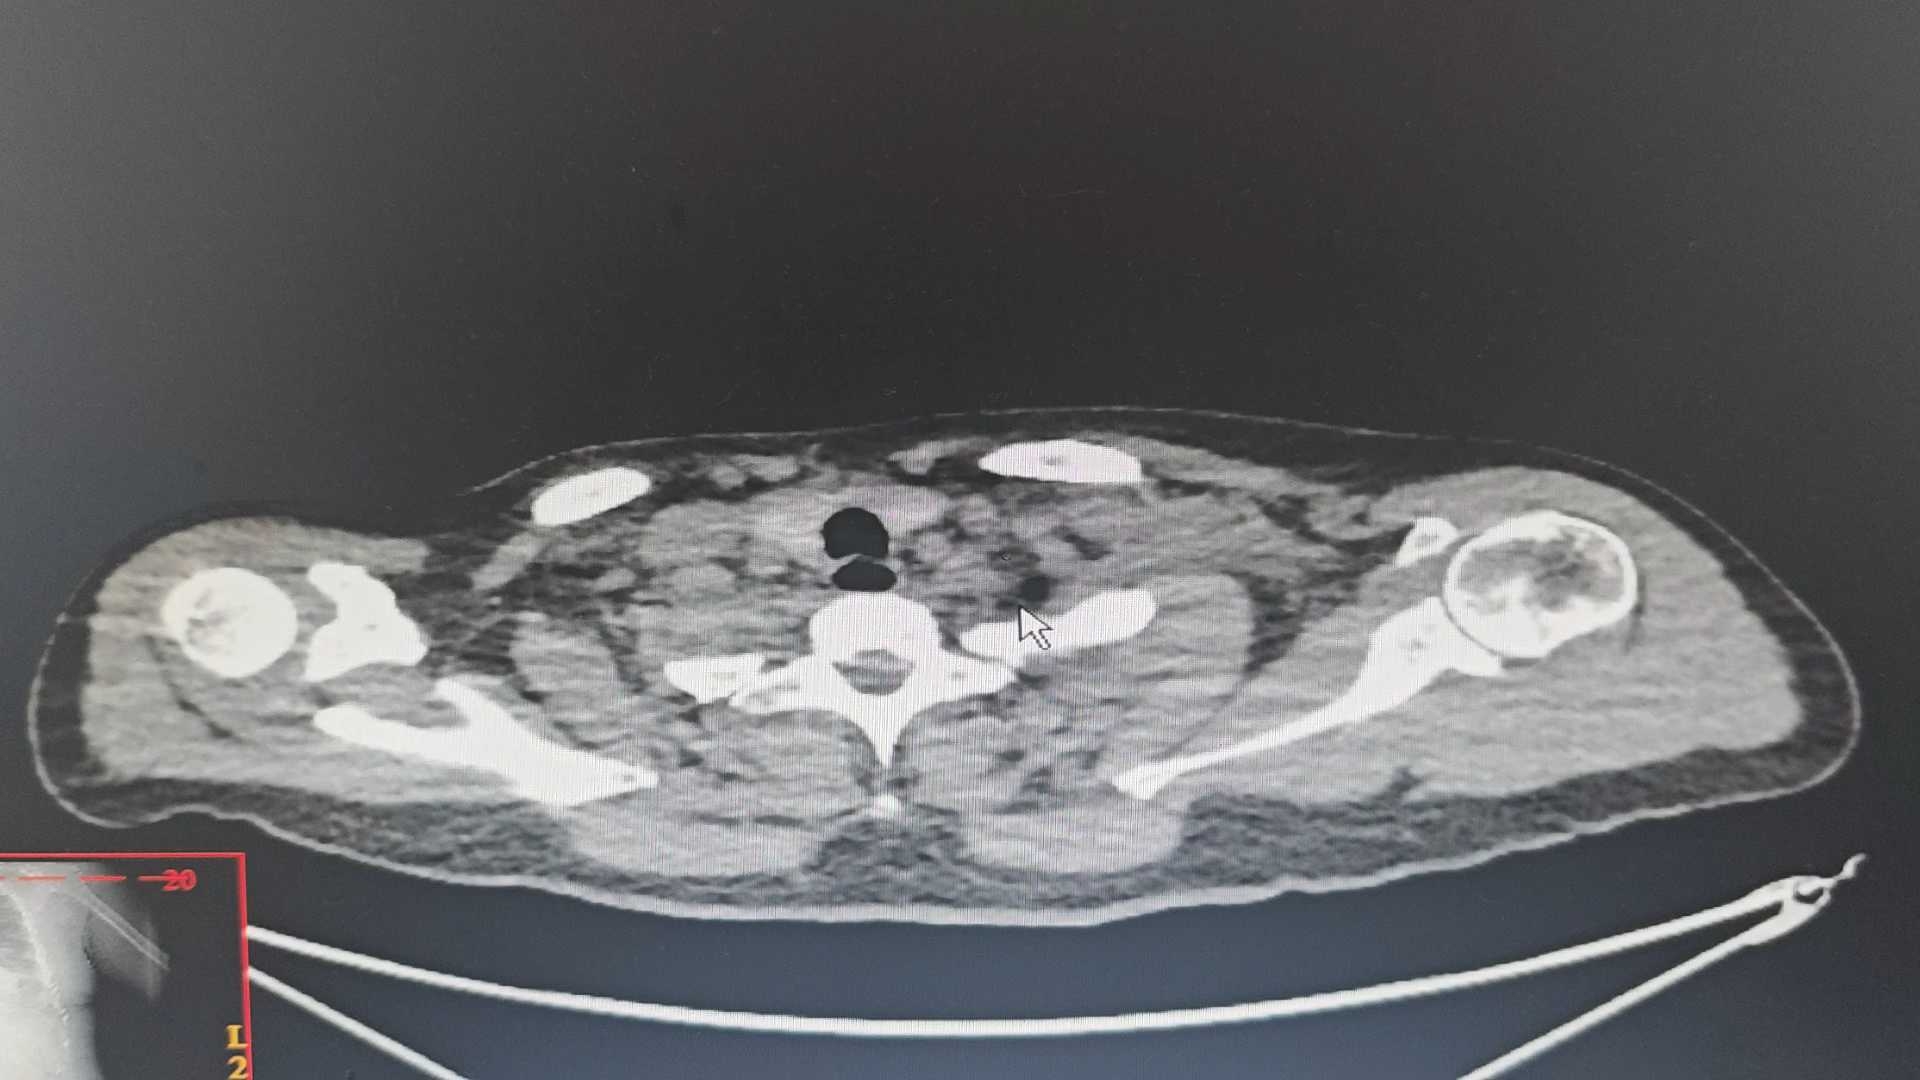

病例如何从影像上明确是肺水肿,还是感染?一叶扁舟独自漂危重急救版达人 · 发布于 10-13 · 来自 Android · IP 安徽安徽459 浏览病例信息病例讨论如图,请老师们解惑。医生必看典型病灶图11971 讨论肺水肿 (74)纠错8 1 1